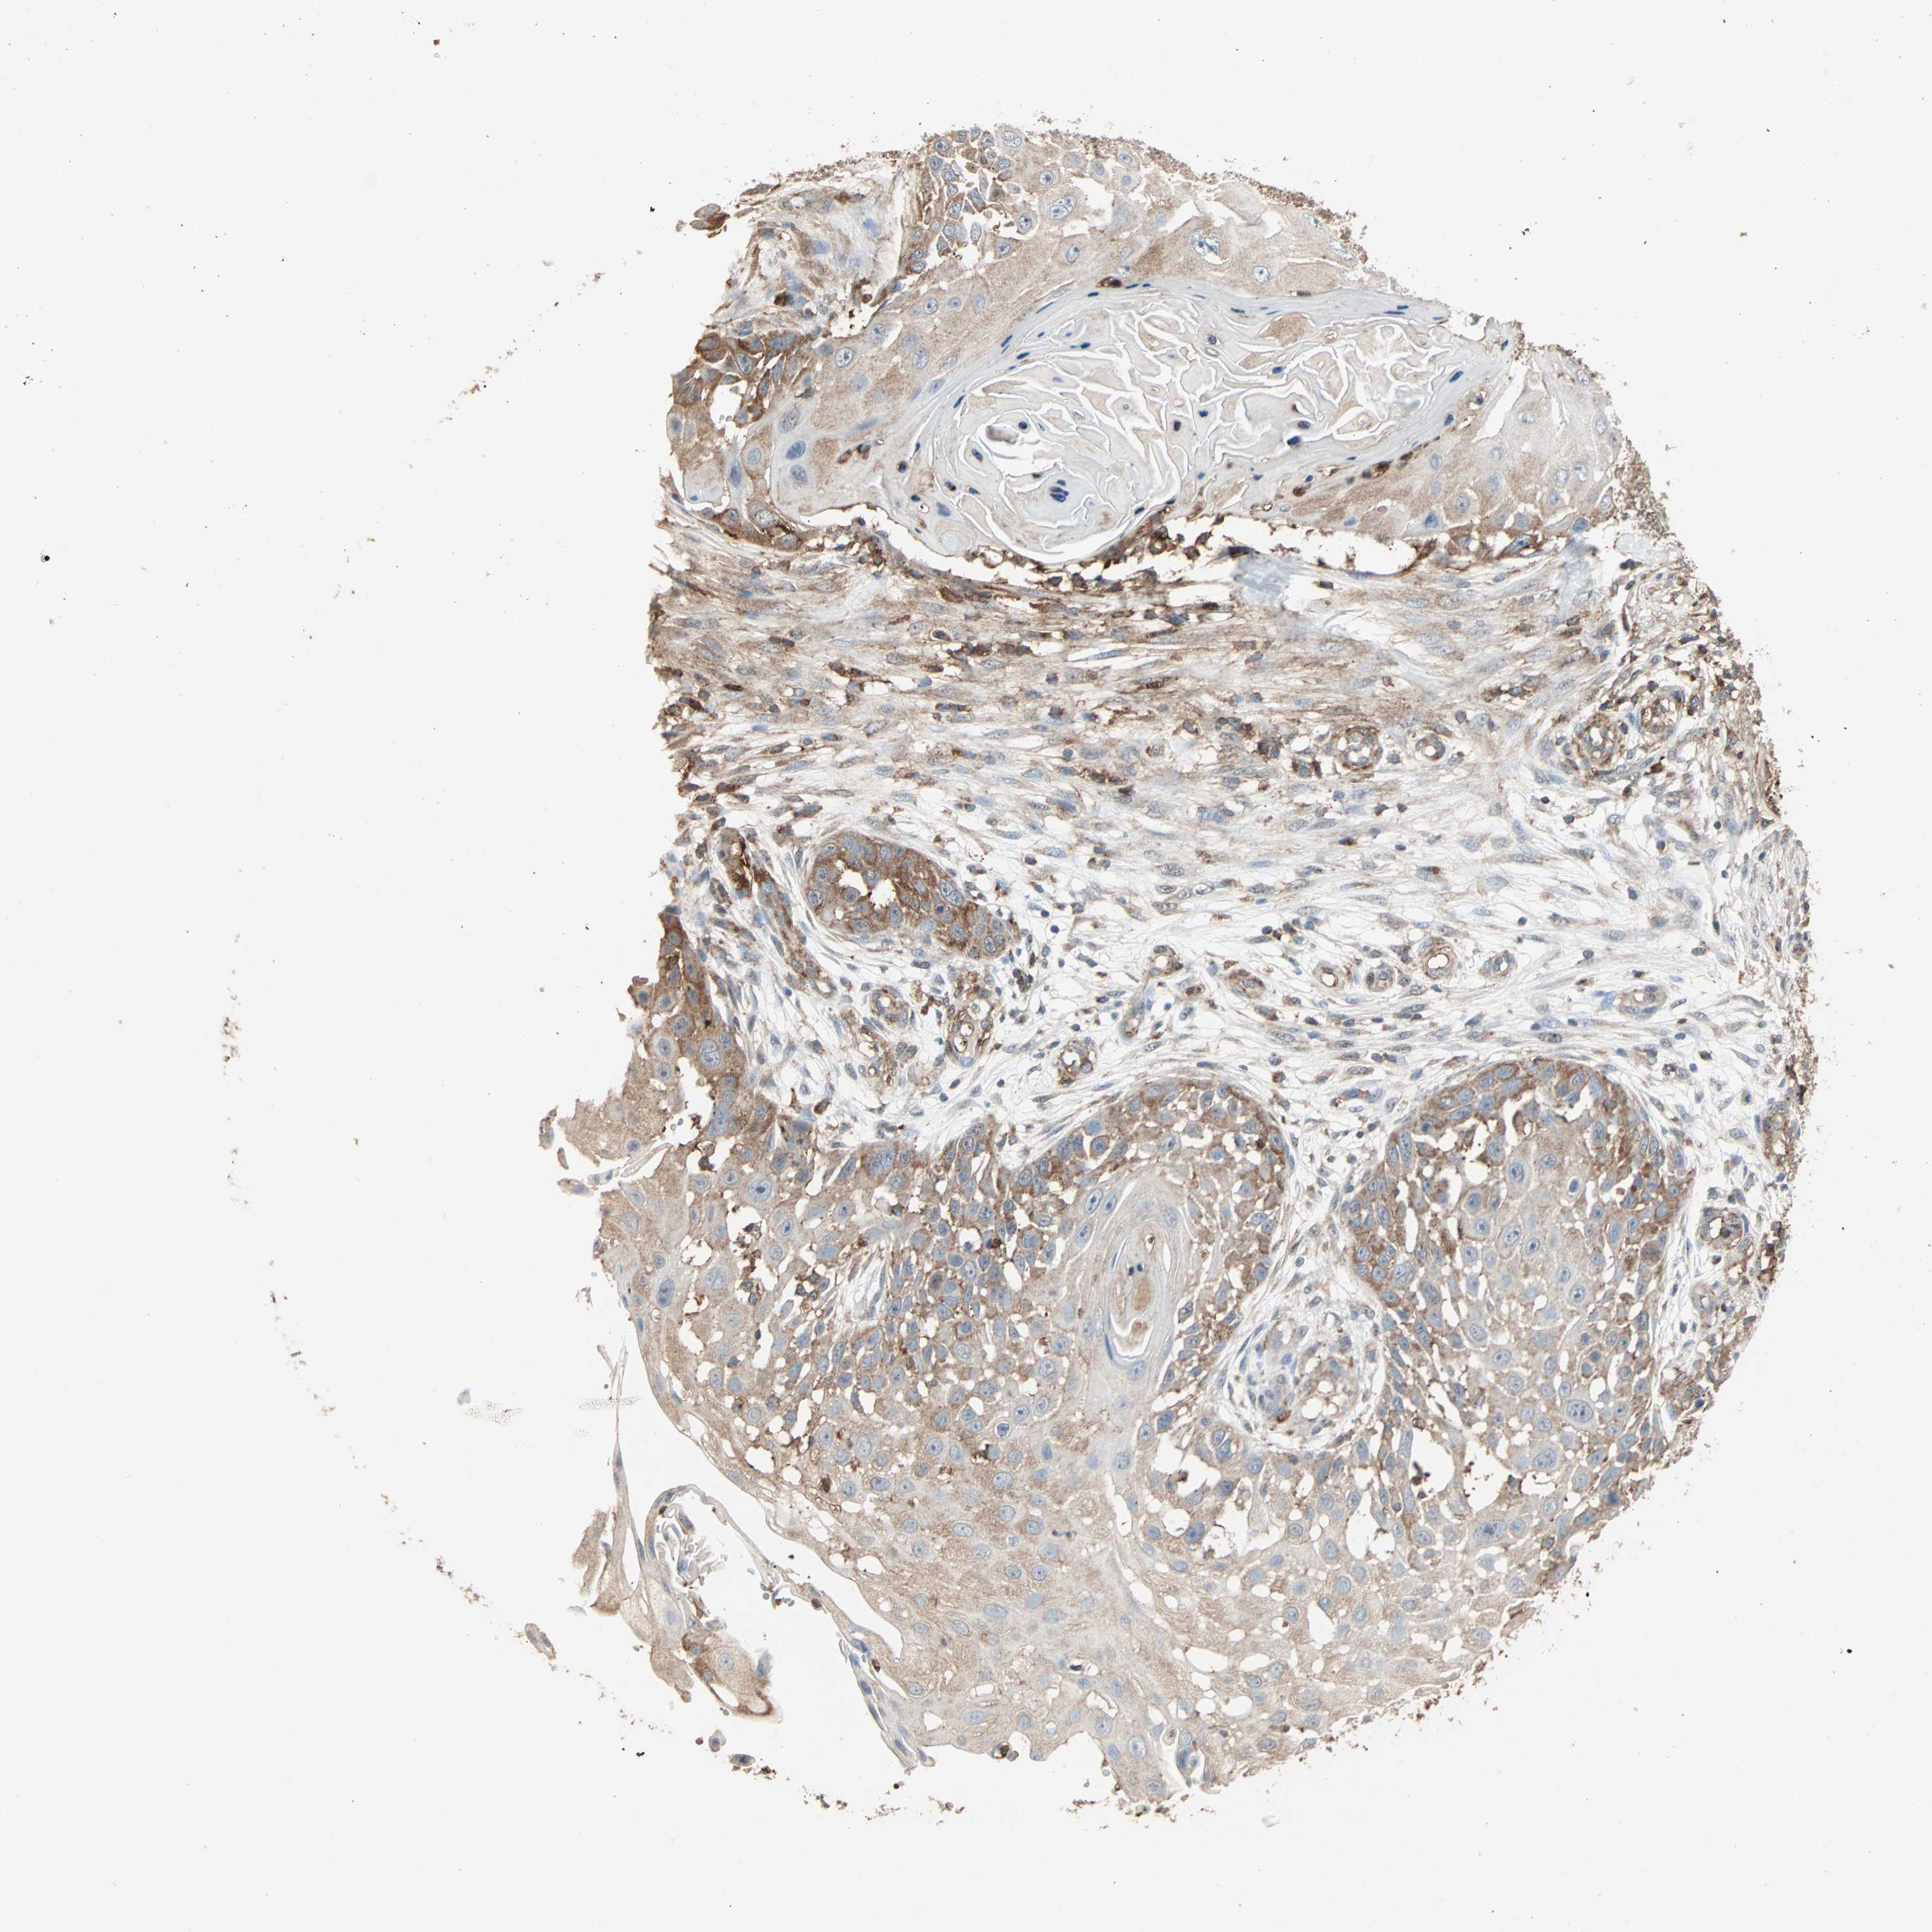

SKIN CANCER - Protein expressioni

A mouse-over function shows sample information and annotation data. Click on an image to view it in a full screen mode. Samples can be filtered based on level of antibody staining by selecting one or several of the following categories: high, medium, low and not detected. The assay and annotation is described here.

Antibody stainingi

Antibody staining in the annotated cell types in the current human tissue is reported as not detected, low, medium, or high, based on conventional immunohistochemistry profiling in selected tissues. This score is based on the combination of the staining intensity and fraction of stained cells.

Each image is clickable and will lead to virtual microscopy that enables deeper exploration of all samples and also displays staining intensity scores, fraction scores and subcellular localization as well as patient and tissue information for each sample.

Antibody HPA007875

Staining

High

Medium

Low

Not detected

Intensity

Strong

Moderate

Weak

Negative

Quantity

>75%

75%-25%

<25%

None

Location

Nuclear

Cytoplasmic/membranous

Cytoplasmic/membranous,nuclear

Basal cell carcinoma